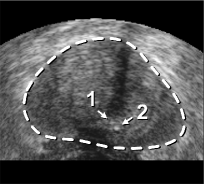

The framework was validated on 278 registrations of 295 US volumes from 17 patients. The 17 reference images were acquired shortly before the intervention, and the tracking images were acquired after a biopsy shot. The clinical protocol was approved by the ethical committee of the XXX hospital, Town, Country, and all patients consented to participate to the study. The images were acquired with a GE Voluson and a RIC5-9 endorectal US probe. The algorithms were executed on a 4-core 2.6Ghz processor. In order to provide a reference gold standard for the evaluation of registration accuracy, experts manually segmented 467 point fiducials that were clearly identifiable on multiple images (e.g. calcifications and cysts). The distances between fiducial pairs were measured after registration to estimate the local accuracy. Note that the unavoidable segmentation error increases the measured error in average; this approach hence underestimates accuracy. Accuracy was computed for all registrations that were qualified as valid by experts after visual inspection, which represent 97,8%percent\% of the registrations. The results for both rigid and elastic registration are given in Tab. 1, and a visual illustration of the registration performance is given in Fig. 2. Fig. 3 shows 3D biopsy maps created with our biopsy tracking system.

Figure 2: Fig. (a) shows a prostate volume with calcifications [1,2]. Fig. (b) shows a second volume after rigid registration; low probe pressure led to the low contrast zone [3]. Fig. (c) shows the 3D elastic registration with standard SSD; the whole prostate is dragged towards zone [3]. Fig. (d) shows the 3D intensity shift filtered, inverse consistent elastic registration; the strong intensity differences between both volumes are correctly handled, the calcifications make appearance at the correct position (best viewed in PDF with zoom).